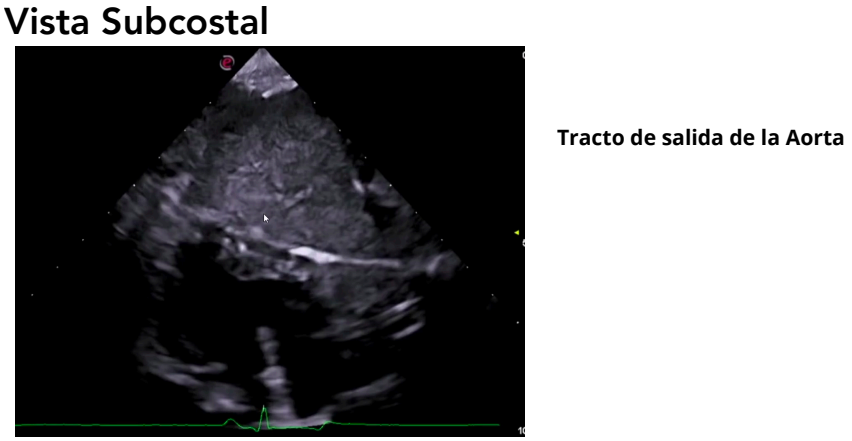

Vista subcostal (subxifoidea)

- Se accede a través de la apófisis xifoides.

- Se usa un transductor de baja frecuencia (2–2.5 MHz).

- Permite estudiar el tracto de salida del VI y la aorta ascendente.

- Alineación ideal para el Doppler, que mide velocidades en aorta.